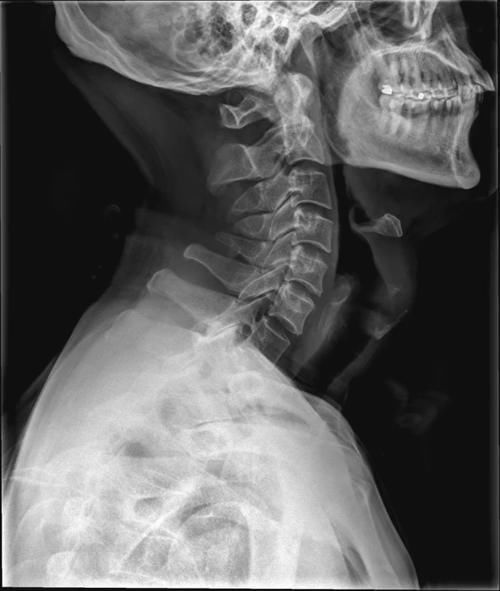

Case4:F,34y;第2、3颈椎棘突骨软骨瘤。

文章插图

Case5:M,47y;颈5后棘突下缘骨软骨瘤。